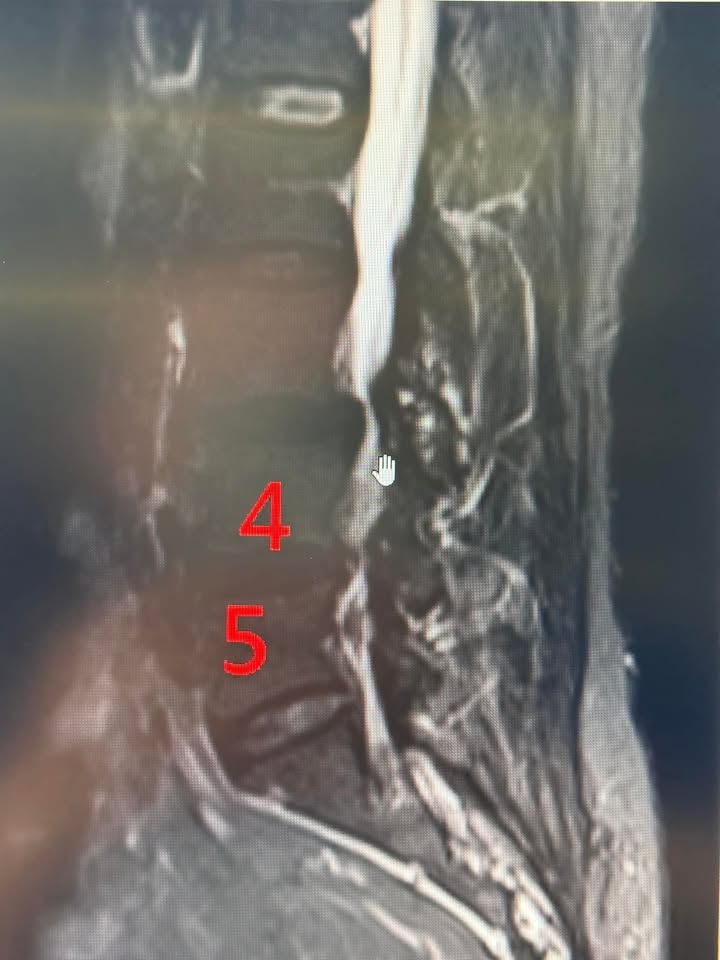

周阿姨年紀六十出頭是一位脊椎狹窄病患,簡單說她是一位深受脊椎狹窄病痛所苦的阿姨,經歷了漫長的痛苦與挑戰後,特別是復健時間長達一年多沒效,又跑去台大神外諮詢是否要開刀,終於找到了一條改善病情的道路——嶄新的微創針刀技術。

這段旅程充滿了驚奇與感動,讓周阿姨對生命充滿了感激與希望,在椎管狹窄疾病的折磨下,去年五月最嚴重時幾乎無法走路,生活變得極度困難。